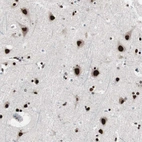

Immunohistochemical staining of human cerebral cortex shows strong nuclear positivity in neurons.